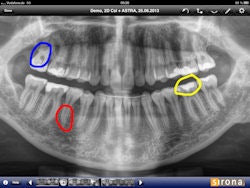

Left: Sidexis iX can be used to analyze x-ray images and insert marks and comments. Right: The new version of the app features a remote connection to Sidexis XG and makes it easier to exchange data with the iPad. All images courtesy of Sirona Dental.